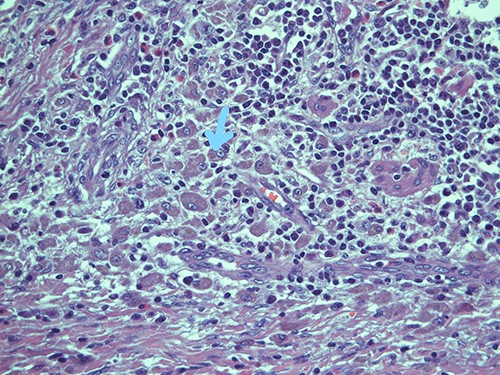

Submucosa is expanded and colonized by a dense histiocytic population (von Hansemann cells) and harboring microcalcifications; haematoxylin and eosin, magnification ×20.

Intracellular and extracellular Michaelis–Gutmann bodies surrounded by inflammatory cell infiltrate of histiocytes; haematoxylin and eosin, magnification ×40.